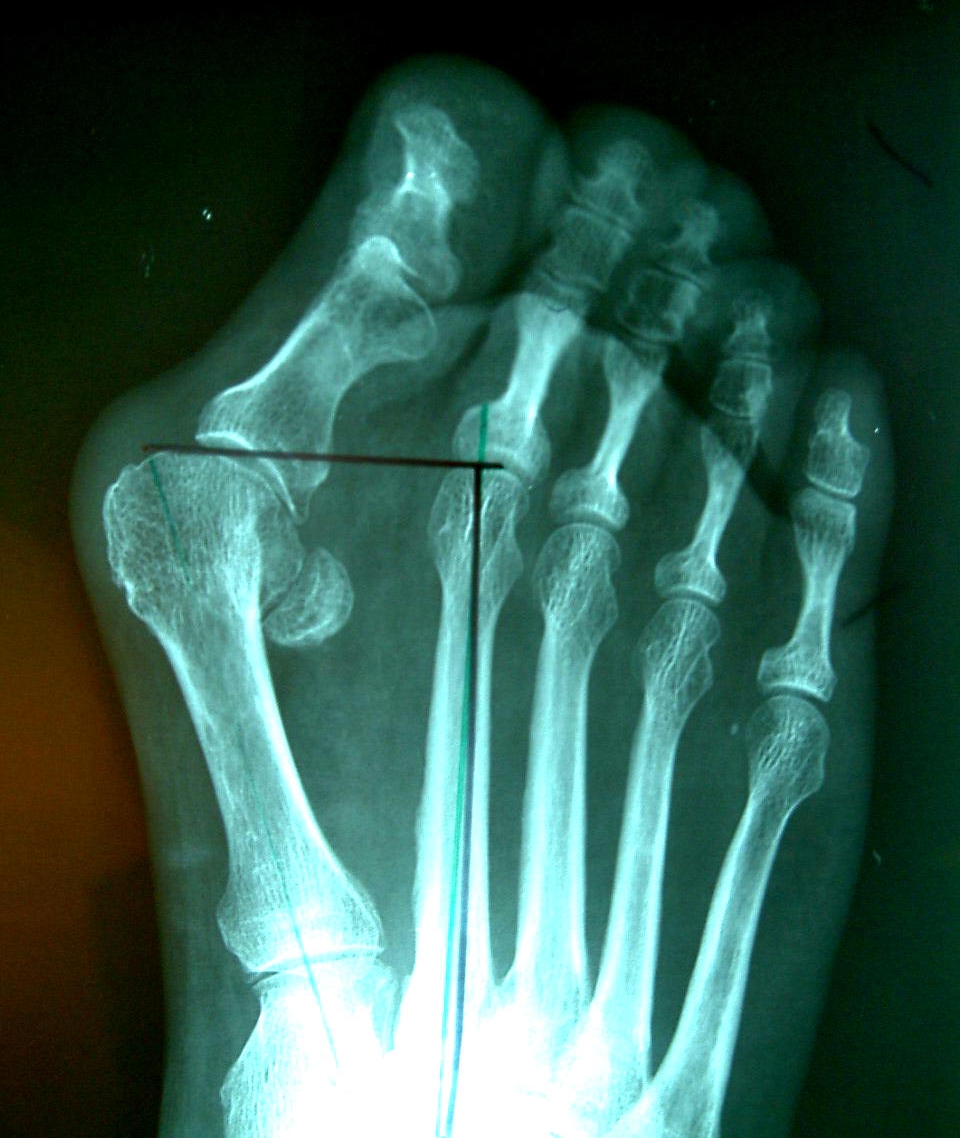

Операция по удалению косточки на большом пальце ноги обычно выполняется на третьей стадии деформации стопы. Эта стадия характеризуется отклонением большого пальца в сторону остальных под углом более 35° и смещением первой плюсневой кости в противоположную сторону под углом более 18°. Эти данные устанавливаются врачом на основе рентгеновского исследования.

Операция по удалению косточки на ноге требует выполнения ряда предварительных мероприятий, которые помогут врачу оценить состояние здоровья пациента. Прежде всего, необходимо проконсультироваться со специалистом, который осмотрит шишку на большом пальце и проанализирует рентгеновские снимки. Рекомендуется сделать рентгенограммы заранее, чтобы не затягивать процесс подготовки. Снимки передней части стопы должны быть выполнены в двух проекциях: боковой и верхней. Консультация важна для установления точного диагноза и определения объема предстоящего хирургического вмешательства.

Помимо рентгенографии, необходимо пройти магнитно-резонансную томографию. Эти исследования помогут определить наличие артроза и других заболеваний костей, степень деформации косточек на ногах, а также угол отклонения фаланг пальца и костей плюсны.